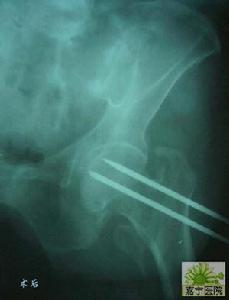

2、閉合經距多根斯氏針內固定

先行脛骨結節牽引,進行復位,行全身系統檢查,傷後3~7d內在骨摺檯上手術。用4枚直徑3.5mm斯氏針同股骨頸骨折多根斯氏針固定術。

Gamma釘固定4、Ender釘固定

釘從股骨內髁上2cm處鑿孔,在X線電視螢光屏上觀察Ender針,穿過骨折部直達股骨頭關節面下0.5cm左右。使數根釘端呈扇形或魚叉樣散開,以固定近端骨塊。術後施皮牽引或防外鏇鞋。

5、Gamma釘固定

90年代初,一些國家採用Gamma釘,即一根帶鎖髓內針,斜穿一根通過股骨頭頸部粗螺絲釘,因主釘通過髓腔,從生物力學分析,力線離股骨頭中心近,因此,Gamma釘股骨內側可承受較大應力,可達到早期下地負重的目的。